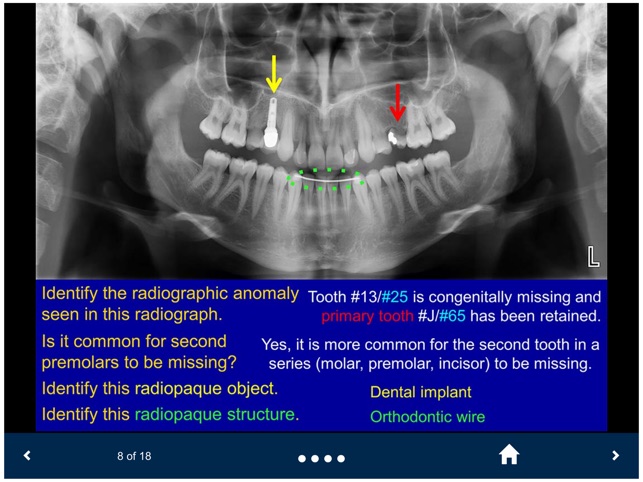

Oral Radiology - SecondLook is an educational self-assessment tool developed by the University of Michigan. The application facilitates learning by presenting a series of high-quality radiographic images, including intraoral, panoramic, and CBCT scans. It utilizes a guided question-and-answer format to help users test their ability to identify anatomical structures, technical errors, and maxillofacial pathologies. This interactive mechanism supports knowledge reinforcement in key areas of oral radiology, from basic anatomy to complex disease presentation.

This application is designed as an educational support resource for dental and health sciences students. Its primary scope is to provide a self-assessment platform for reviewing radiographic images and reinforcing knowledge of oral pathology and anatomy. The tool is intended for study purposes only and is not a substitute for clinical instruction or a diagnostic aid.